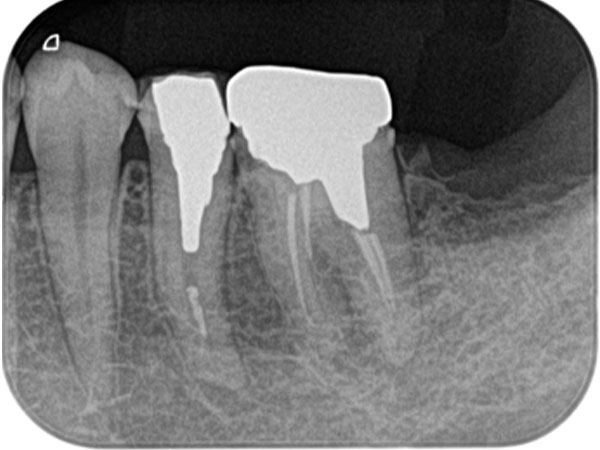

根管治療の仕上げとして、「根管充てん」という工程があります。神経を除去したことによってできた空洞を充てん剤で埋めて、すき間がないように緊密にふさぎます。すき間を残してしまうと、ここから再び細菌が侵入し、症状が再発する危険性があります。

一般的な保険診療では、「ガッタパーチャ」というゴムのような充てん剤を利用しますが、ガッタパーチャではすき間ができやすく、再発しやすい原因のひとつになっています。

そこで、当院では「MTAセメント」という充てん剤を利用します。MTAセメントは硬化の際にわずかながら膨張する性質があり、根管内をすき間なく埋めるのに適しています。また、とても固く、神経を取り除いた歯を内部から補強する効果もあります。さらに殺菌作用や歯の組織を再生させる効果があり、治療後の経過が良好になります。

根管治療がうまくいかなかった場合、歯の根の先端に膿がたまることがあります。膿が溜まっている袋が大きいと抜歯になりますが、そうでない場合は外科的な処置で治療できることがあります。歯茎を切開して歯の根を切断し、膿の袋を摘出します。この処置を「歯根端切除術」といいます。

術前

術中

術後